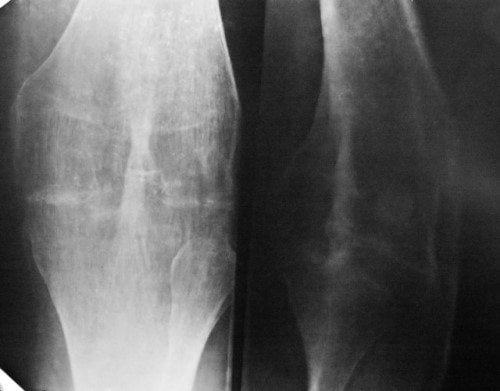

В ортопедии и травматологии остеоартроз классифицируют в зависимости от степени изменения хрящевых и костных структур, определяемой с помощью рентгенографии. Для каждой из них характерна своя клиническая картина.

Третья |

Деформация опорной площадки выражена, изменена ось конечности. Суставная сумка становится жесткой, образуются обширные костные наросты, сращивается суставная щель. Боли становятся постоянными, полностью или частично обездвиживается сочленение |

Методы диагностики

- рентгенография;